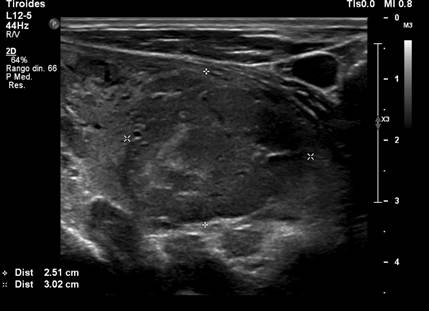

One year later, a follow-up PET-CT scan showed a decrease in the size and metabolism of cervical lymph nodes; however, a pulmonary nodule was present in the left lower lobe (13 mm), along with left hilar lymphadenopathy (12 mm), findings consistent with systemic tumor progression (Figure 2).

Figure 2

Thoracic PET-CT. Left hilar lymphadenopathy measuring 12 mm, hypermetabolic (SUV LBM 3), suggestive of metastatic origin.

Source: SOLCA Intranet - Guayaquil.